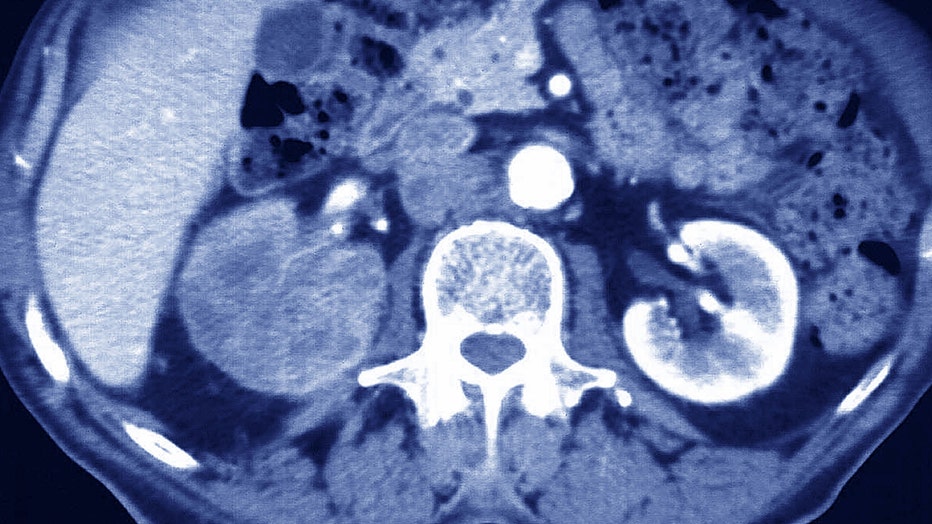

renalcarcinoma

Renal Carcinoma, Scan, Carcinoma Of The Right Kidney, Primary Tumor, visualized By Abdominal Scanner of 79-Year-Old Man. (Photo By BSIP/Universal Images Group via Getty Images)

"It looked like certain brain cancers or renal cancers had these inhibitory markers, so perhaps those tumors might benefit from this type of vaccine where you could alter the tumor microenvironment," Seder continued, adding that more testing will need to be done to understand which tumors respond to the vaccine.